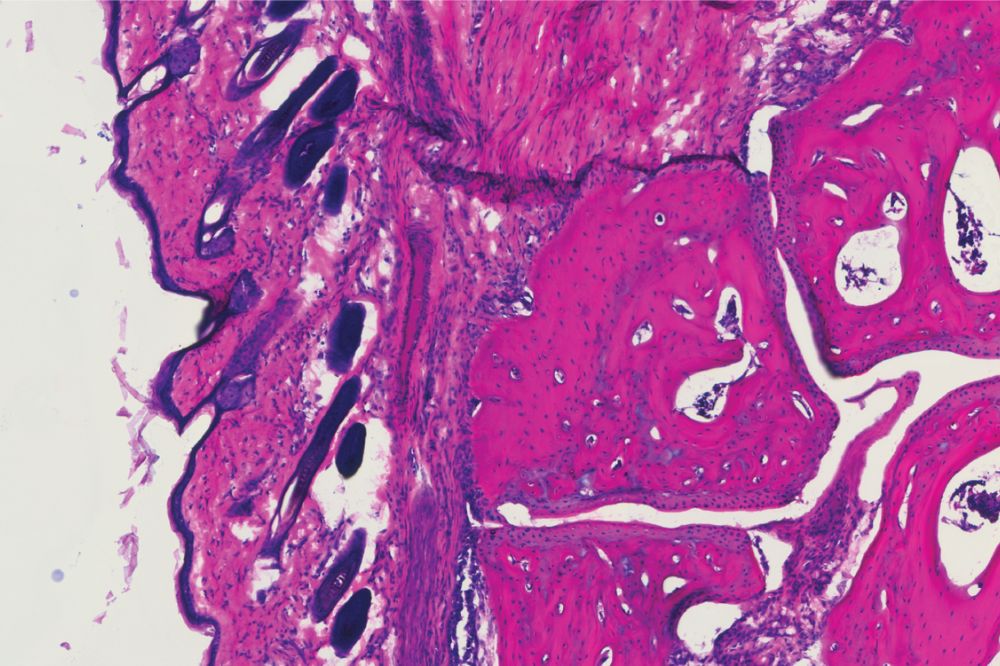

A histology showing the ankle joint of a mouse four days after receiving the new antibody treatment, V11 sFc (Ravetch lab)

They next engineered a recombinantly expressed IgG to have enhanced binding to these receptors and infused them into mice with human Fc receptors into which they had induced arthritis (meaning they'd been injected with serum isolated from a mouse with naturally occurring arthritis). A similar group of arthritic mice was treated with the conventional IVIG infusion.

Both groups benefited from the infusion, seeing reduced joint swelling. But the doses were dramatically different: 100 times as much IVIG was required to achieve the same effect as one dose of the new molecule.